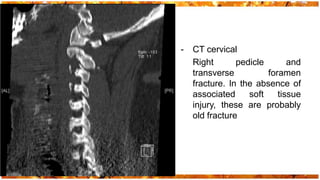

-   CT cervical

Right       pedicle       and

transverse          foramen

fracture. In the absence of

associated     soft    tissue

injury, these are probably

old fracture

- CT cervical Right pedicle and transverse foramen fracture. In the absence of associated soft tissue injury, these are probably old fracture